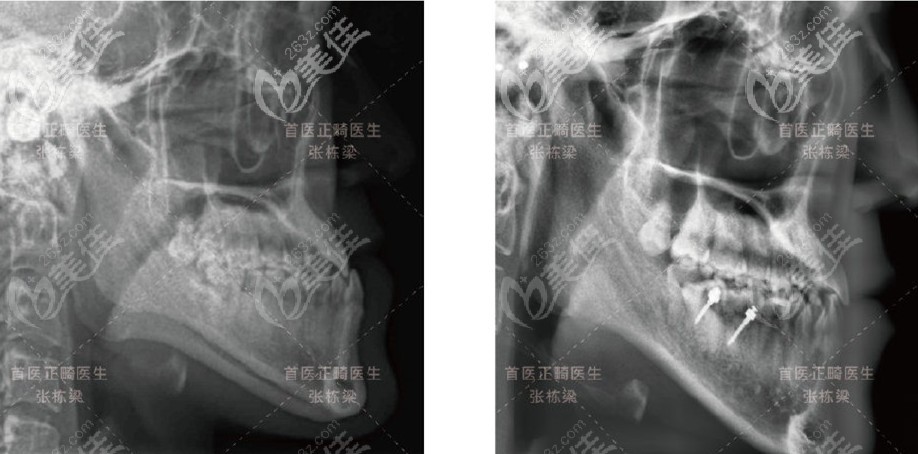

利用种植支抗整体远移下牙列,解除反颌,并增加上前牙负转矩以及下颌前牙的正转矩,等前牙反颌解除后,升高下颌后牙,倾斜颌平面,促使下颌向下向后旋转。